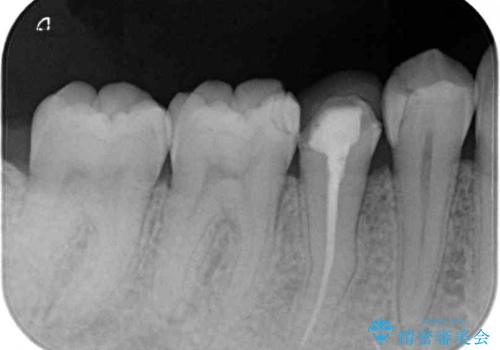

- 神経を抜く処置の後に装着したプラスチックのクラウンが外れてしまったとのことで来院された患者様です。

患者様自身、神経の取り除かれた歯はしっかりと製作されたクラウンを装着するべきと理解していただいていたため、オールセラミッククラウンにて補綴治療することとしました。